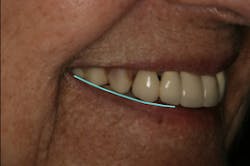

There was some fine-tuning to the patient's occlusion during the healing period. Nevertheless, the goals of treatment were accomplished very predictably. Figures 21 (horizontal position) and 22 (vertical position) verify both the new vertical and horizontal positions of the upper incisal edge.

Understanding the patient’s masticatory system requires the dentist to gather the correct data through a comprehensive examination. (6) In addition, diagnostic records (mounted models in centric relation and digital photography) can be used to provide predictable results. The overall esthetic outcome, along with improved function, gave the patient a new outlook on life and increased confidence—all within her budget (figures 23–25). The Dawson Academy is a great resource for learning about the masticatory system, functional esthetics, and a predictable treatment-planning protocol.